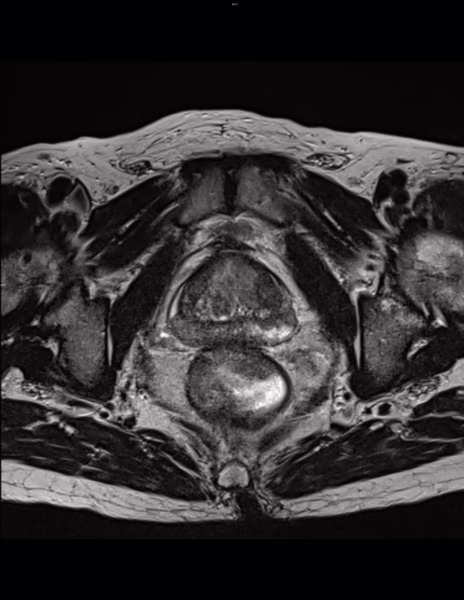

Zona Periférica:

Se identifican cambios hemáticos dispersos en ambas zonas periféricas evidentes hiperintensidades difusas en secuencia T1 y T1-FATSAT, no muestran restricción hídrica en difusión, relacionado con antecedente conocido.

Zona de Transición:

En ambas zonas transicionales destacando del lado izquierdo a nivel anterior y medial corresponde a un nódulo hiperplásico de contornos definidos que muestra cambios hemáticos como hiperintensidad en T1 y T1-FATSAT.

T2: Se observan nódulos hiperplásicos encapsulados y parcialmente encapsulados. Categoría 2/5.

DWI: Hipointensidades lineales en ADC. Categoría 2/5.

DCE: Realce focal temprano negativo.

PI-RADS 2.

Cambios hemáticos dispersos en ambas zonas transicionales y periféricas predominantemente en estas últimas, relacionados con antecedente conocido.

Hipointensidades lineales y cuneiformes en zona periférica bilateral sugerentes de cambios secuelares por antecedentes de prostatitis crónica de repetición.